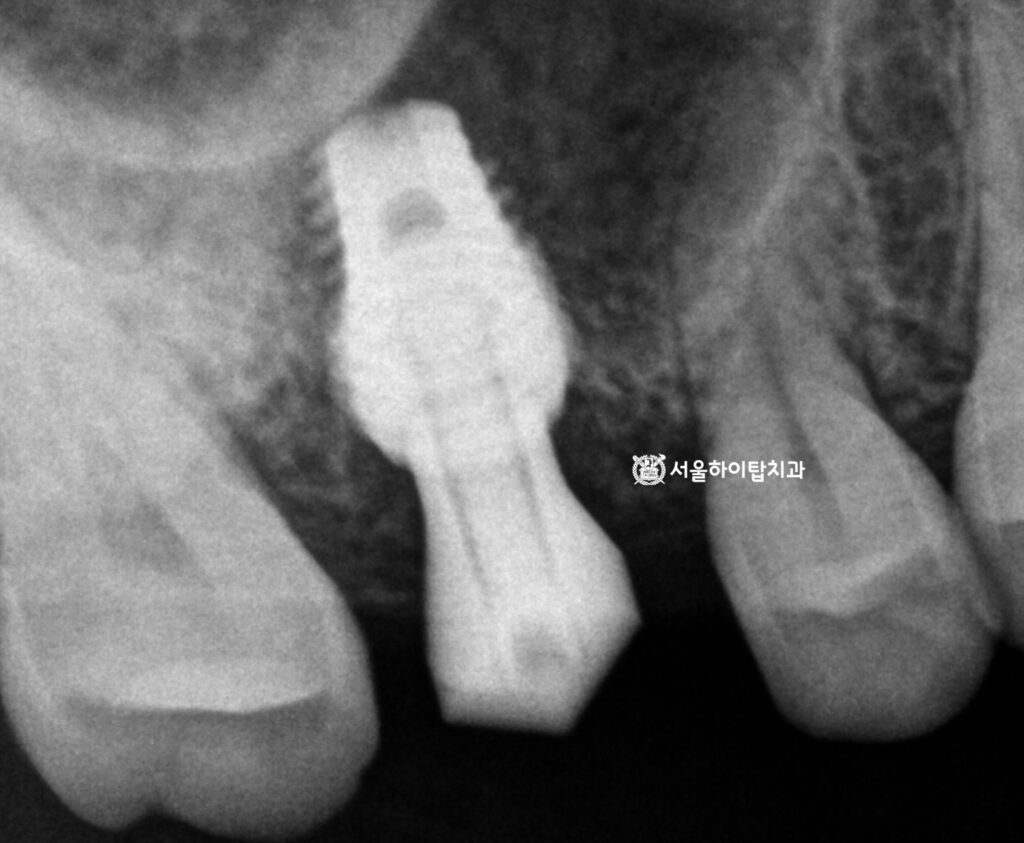

이어서 반대편으로 넘어가면,

치관부 중앙에서 치근단까지 이어지는

명확한 파절선(fracture line)이 관찰됩니다.

이는 단순 균열을 넘어

치근 파절(root fracture) 로

진행된 상태로 볼 수 있습니다.

현재 양쪽 모두에서

문제가 발생한 상황이므로,

정밀한 진단과 치료 계획 수립을 위해

CT 촬영이 필요합니다.

다만 뿌리까지 이어진 fracture line은

그 상태로 오래 유지되기 어렵습니다.

그 이유는, 씹는 힘 등

저작력이 지속적으로 가해지면서

치근이 미세하게 흔들리기 때문입니다.

또한 내부 치수가 염증을 일으키면

주변 치주조직과 치근단에 압박과 자극이 생겨

파절선이 점차 확장되거나 치아 구조가 약해져

더 이상 안정적으로 유지되지 않습니다.

즉, 동암 치과 에서 쉽게 말씀드리자면,

장기적인 안정성이 부족한 상태인 셈입니다.